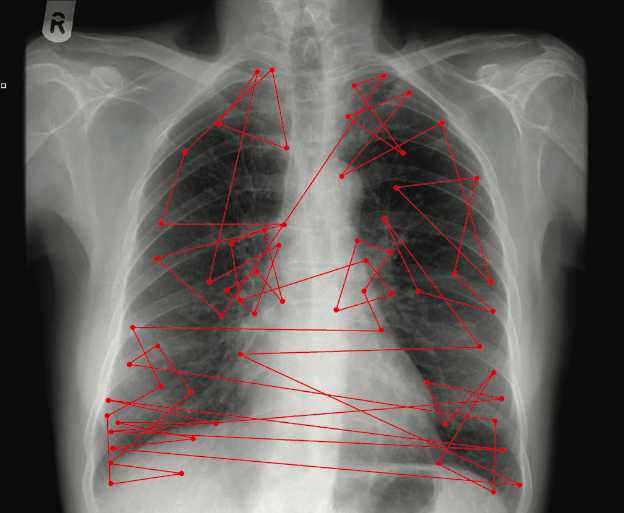

Figure 1: An example of fixations across a chest radiograph and the visual search pattern constructed by them. Image courtesy of the Ad- elaide and Meath Hospital, Dublin.

The field of view in humans extends over 180° but it is only the centre of this visual field that provides sharp detailed vision. Consequently, eyes move to bring interesting features into this centre. The pause over the point of interest is known as a foveal fixation. Fixations are characterised by their multiple (clustering) nature when observers dwell extensively on a location, as the eyes do not remain stationary for long before losing sensitivity [13]. Eye-tracking experiments assume that fixations represent the location of conscious attention of the viewer. The eye movements of an observer over an image can be tracked with remote, infrred pupil-corneal reflection cameras which group these fixations into search patterns (Figure 1). The use of visual search patterns provides an organisational framework for studying basic perceptual processes that can be applied to the understanding of abnormality detection. It is useful for classifying detection failures and has suggested methods for improving perceptual performance [14]. The following paragraphs outline two important aspects of visual search, namely, aspects leading to failure and where in the sequence they occur, and aspects leading to success by examining the visual search patterns of experts.